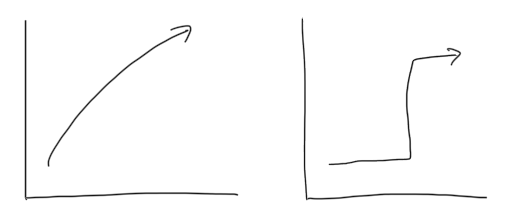

本病態は大-小動脈が段階的/多発性に障害されるという特徴があり、神経症状も血管病変の病歴をとります。通常の感染症では急性経過となりますが、この病態では突然発症/段階的な悪化という特徴があり、病歴で区別することが診断に重要です。

前述の通り、本病態は大-小動脈が段階的/多発性に障害されるという特徴があります。そのため病変は皮髄境界に好発し、多発・両側性で時間差で増加してくるような経過をとります。MRAでは分節状狭窄や後拡張を認めることがあります。素人目には、若年者や血管リスクが高くない患者なのに、MRAで血管ボロボロという感じに見えます。